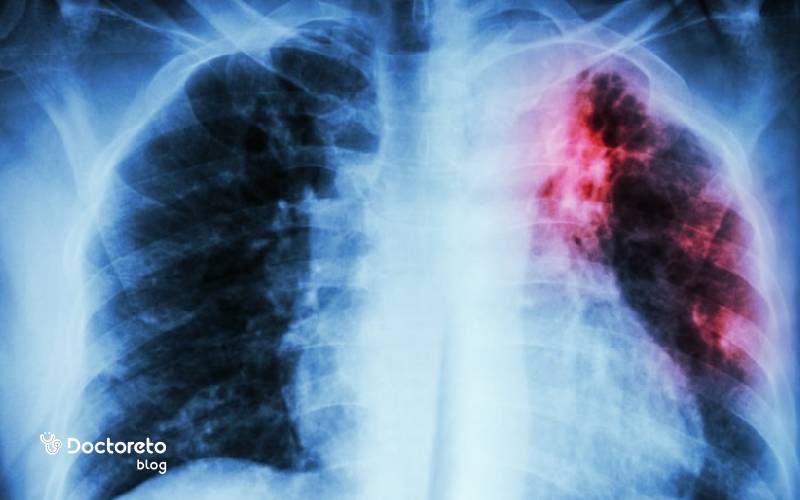

رادیولوژی عفونت ریه

رادیوگرافی قفسه سینه نخستین ابزار تصویربرداری برای ارزیابی الگوی درگیری ریه است و میتواند تراکم لوبار، ارتشاح بینابینی یا نشانههای آب آوردن ریه را نشان دهد. در موارد پیچیدهتر یا وقتی عکس ساده کافی نیست، سی تی اسکن جزئیات بیشتری از محل و وسعت التهاب و وجود آبسه یا آمپیم به دست میدهد. تفسیر دقیق تصاویر به تصمیم درباره نوع آنتی بیوتیک، نیاز به بستری یا مداخله کمک میکند. پایش تصویری در طول درمان نیز روند بهبود یا لزوم تغییر رویکرد را نشان میدهد.